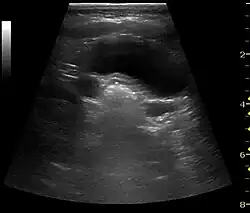

Kidney stone disease

Even though US has a lower sensitivity and specificity than CT for the detection of kidney stones (urolithiasis), US, if available, is recommended as the initial imaging modality in patients with renal colic and suspected urolithiasis. US has no risk of radiation, is reproducible and inexpensive, and the outcome is not significantly different for patients with suspected urolithiasis undergoing initial US exam compared to patients undergoing initial CT exam.[1]

With US, larger stones (>5–7 mm) within the kidney, i.e., in the calyces, the pelvis and the pyeloureteric junction, can be differentiated, especially in the cases with accompanying hydronephrosis (Figure 18 and Figure 19). Hyperechoic stones are seen with accompanying posterior shadowing. Additional twinkling artifacts below the stone can often be seen using Doppler US. Large stones filling the entire collecting system are called coral stones or staghorn calculi and are easily visualized with US (Figure 20). Stones in the ureters are usually not visualized with US due to the air-filled intestines obscuring the insonation window. However, ureteral stones near the ostium can be visualized with a scan position over the bladder. An exam of the ureteric orifices and the excretion of urine to the bladder can be performed by inspecting the ureteric jets in the bladder with color Doppler US.

Figure 19. Centrally located stone with posterior shadowing. No hydronephrosis is present. Measurement of kidney length on the US image is illustrated by '+' and a dashed line.[1] -

Figure 20. Staghorn calculi filling the entire collecting system and creating pronounced shadowing.[1] -